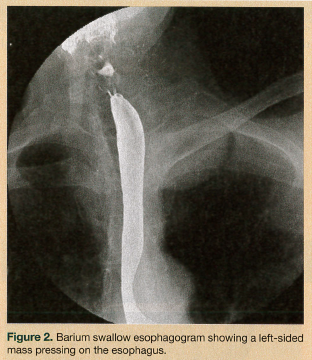

On physical examination, the patient had a body mass index of 22.4. She was hemodynamically stable and well oriented, with no evidence of neurological deficit. Her oropharynx was clear and her uvula was erythematous. Saliva drooled from the angle of mouth, with no clinical suggestion of aspiration. An attempted upper esophageal endoscopy revealed obstruction of the upper esophagus and blackish discoloration of the esophageal mucosa, and it could not be completed. A chest radiograph and electrocardiogram were unremarkable. Fiberoptic laryngoscopy ruled out an upper airway lesion, but showed posterior glottic edema. Computed tomography (CT) scans of the neck and chest added to the confusion, showing a soft-tissue density surrounding the proximal esophagus and a possible 2.5-cm homogenous attenuated paraspinal density (most likely a nerve sheath tumor) in the left upper lobe (Figure 1). A barium swallow esophagram was performed, which showed the esophagus being compressed by the mass (Figure 2). Magnetic resonance imaging of the patient’s head and neck revealed a circumferential mass lesion around the proximal esophagus and a left paraspinal round, well-circumscribed area representing a mass or complex cyst.